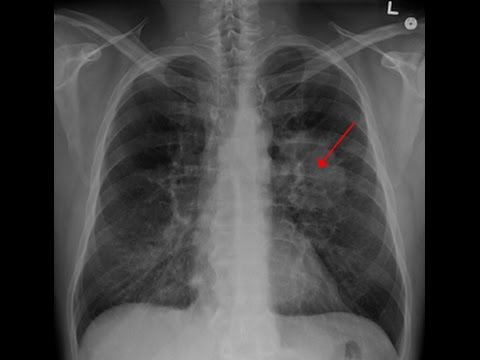

Ung thư phổi có lây qua đường hô hấp